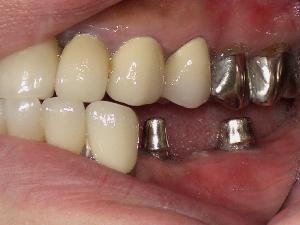

STEP6 上部構造の設置

STEP7 上部構造のチェック